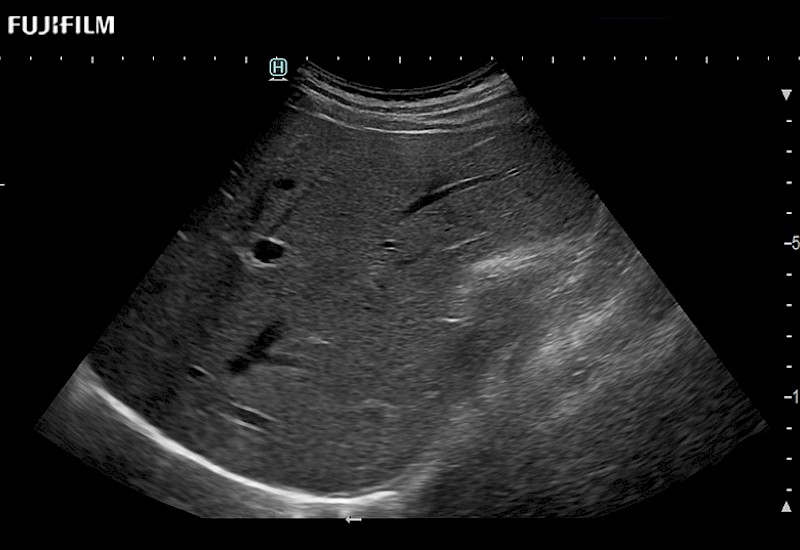

The ARIETTA 750 incorporates all of the proven technologies and functions that medical professionals have come to expect from Fujifilm Healthcare.

ARIETTA 750 is the definitive diagnostic ultrasound solution for any clinical setting - Private Office, Imaging Center, or Hospital. The ARIETTA platform provides the ultimate in clinical performance with its state-of-the-art features and large user-friendly display.

The ARIETTA 650 DI combines trusted Fujifilm Healthcare technologies and features tailored for surgical oncology.

Designed to meet the demands of surgeons, the ARIETTA 650 DI offers precise guidance. Its advanced capabilities and large, intuitive display offer accurate and efficient care in operating rooms and specialized surgical settings.